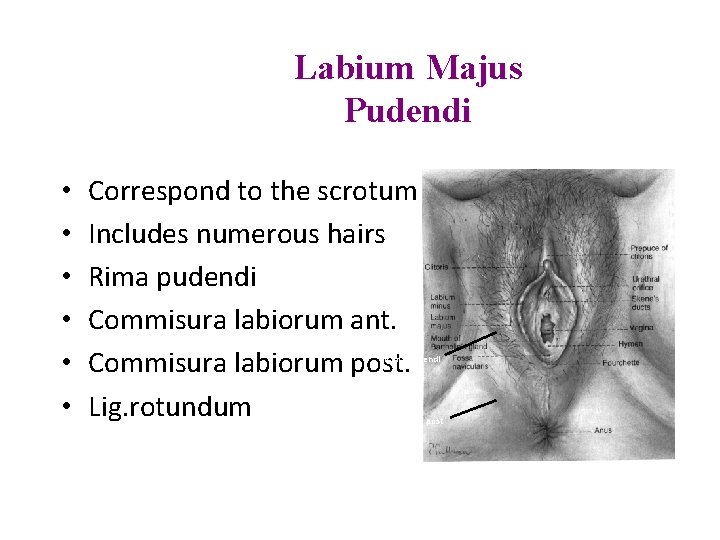

Labium Majus Pudendi • • • Correspond to the scrotum Includes numerous hairs Rima pudendi Commisura labiorum ant. Commisura labiorum post. Lig. rotundum Rima pudendi Commissura post

Labium Minus Pudendi (Nymphae) • • Includes sweat glands Preputium clitoridis Frenilum clitoridis Sulcus nympholabialis Frenulum labiorum pudendi Fossa navicularis Fourchette Sulcus nympholabialis Frenulum labiorum pudendi Frenulum clitoridis